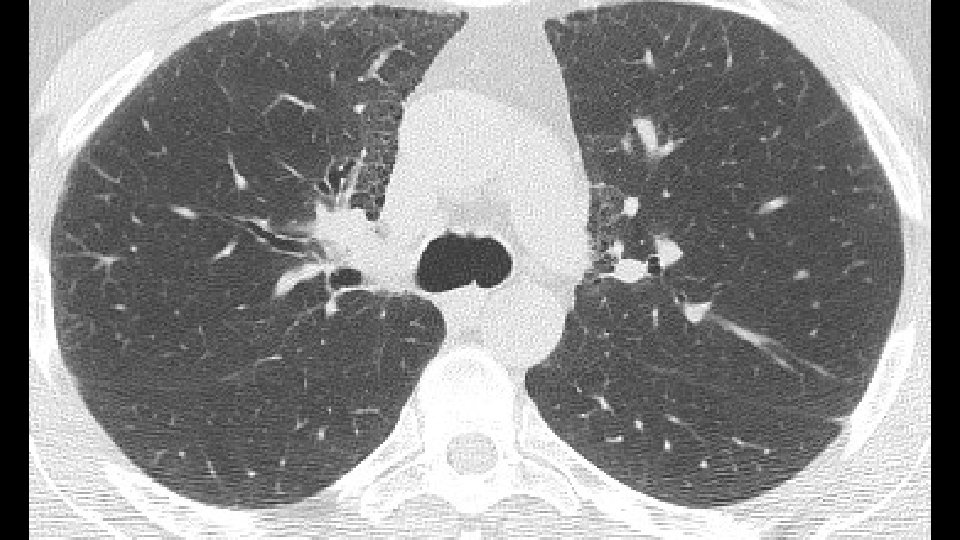

Bronchovascular ground glass attenuation + subpleural sparing D. D. f. NSIP vs inconsistent UIP (GG and bronchovascular distribution)